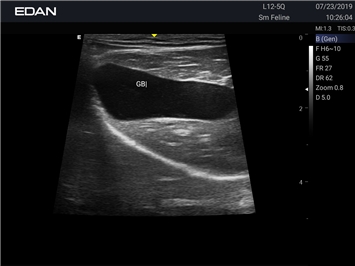

Ветеринарный ультразвук одним нажатием. Система Acclarix AX2 VET разработана с целью обеспечить бескомпромиссную производительность по доступной цене. Наличие уникальных двойных аккумуляторов в легком корпусе массой 4,5 кг из магниевого сплава позволяет системе Acclarix AX2 VET удовлетворять все потребности ветеринарных исследований, сохранив низкую стоимость.

EDAN Acclarix AX2 VET представляет собой специализированную ветеринарную ультразвуковую систему, сочетающую высокую производительность с доступной ценой. Благодаря продуманной конструкции и передовым технологиям, система обеспечивает качественную диагностику животных различных видов.

• Высокое разрешение для детальной диагностики

• Улучшенная визуализация глубоко расположенных органов

• Непрерывная автоматическая оптимизация изображения

• Адаптация к особенностям анатомии разных видов животных

• Повышенная точность исследований